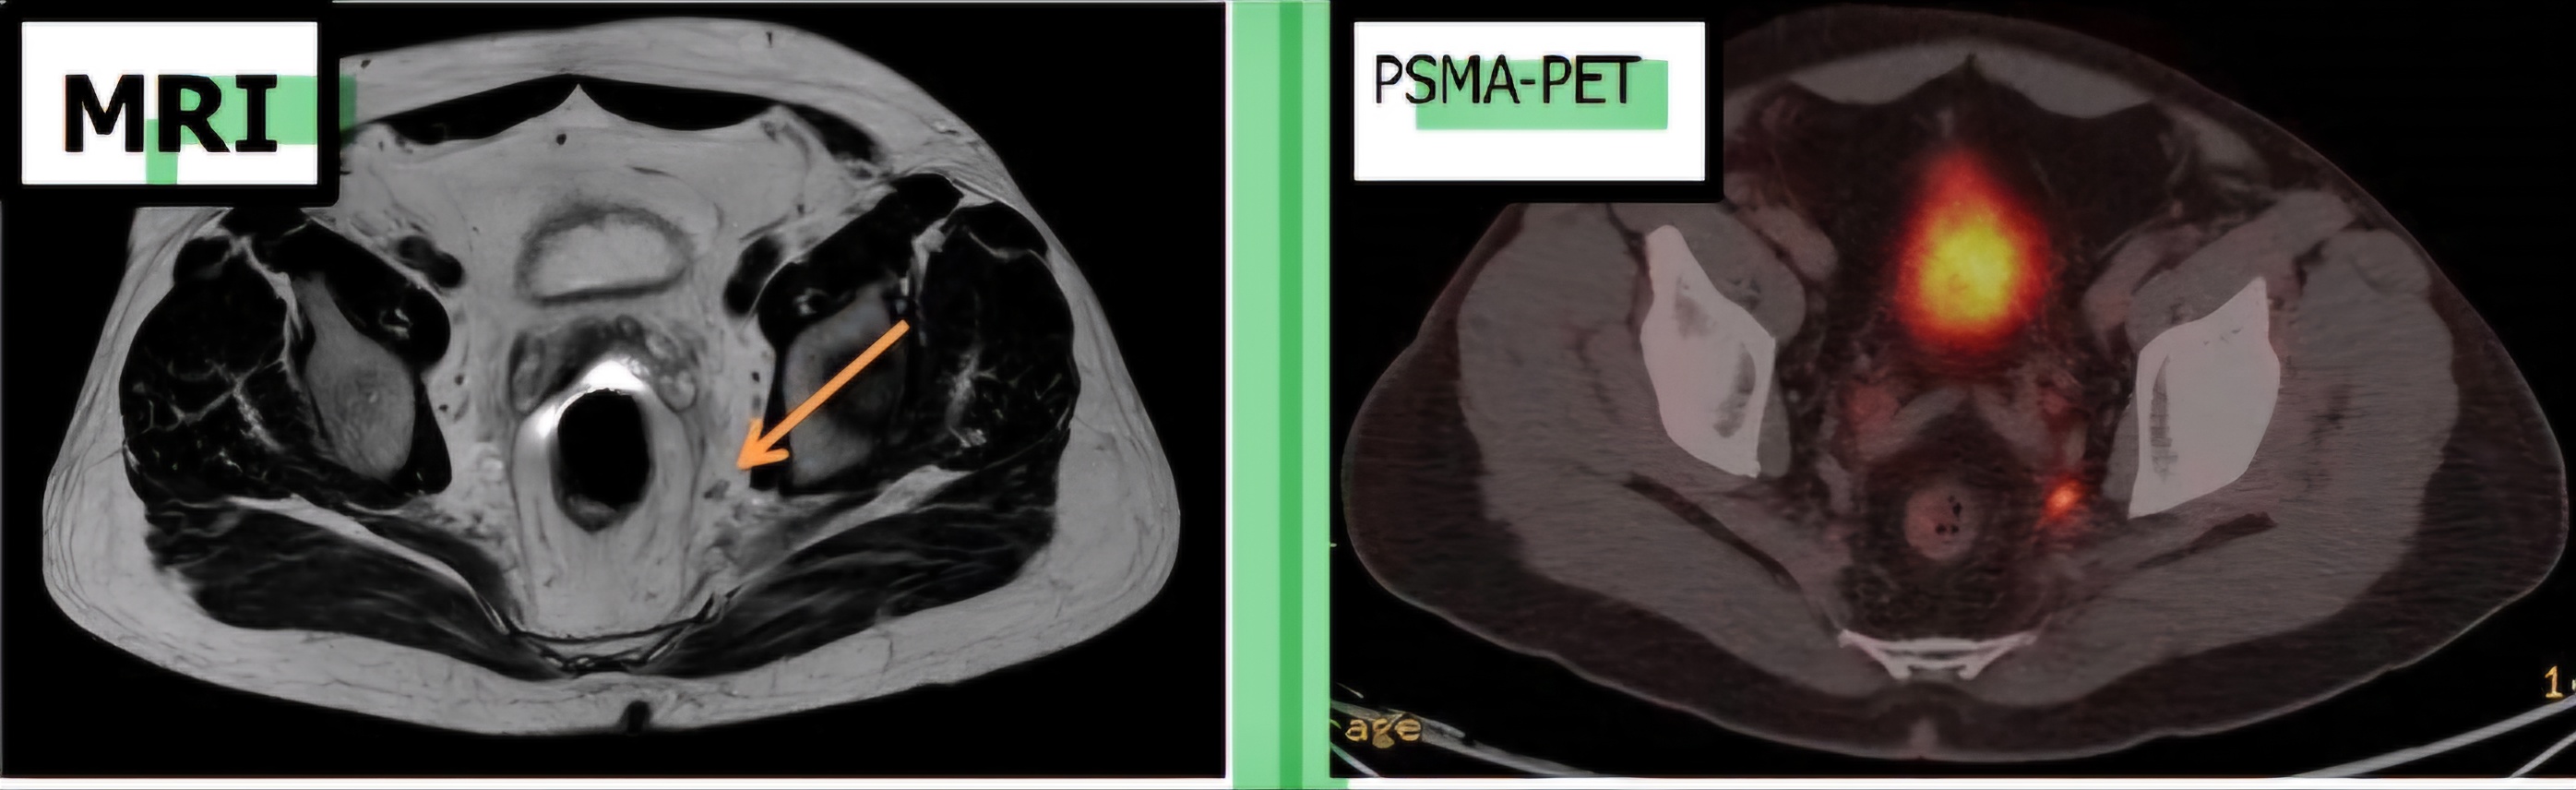

MRI와 PSMA-PET 이미지

MRI는 작은 병변의 진단이 어려운 경우가 있으며 PSMA-PET 검사를 통해 진단 정확도가 향상됩니다.